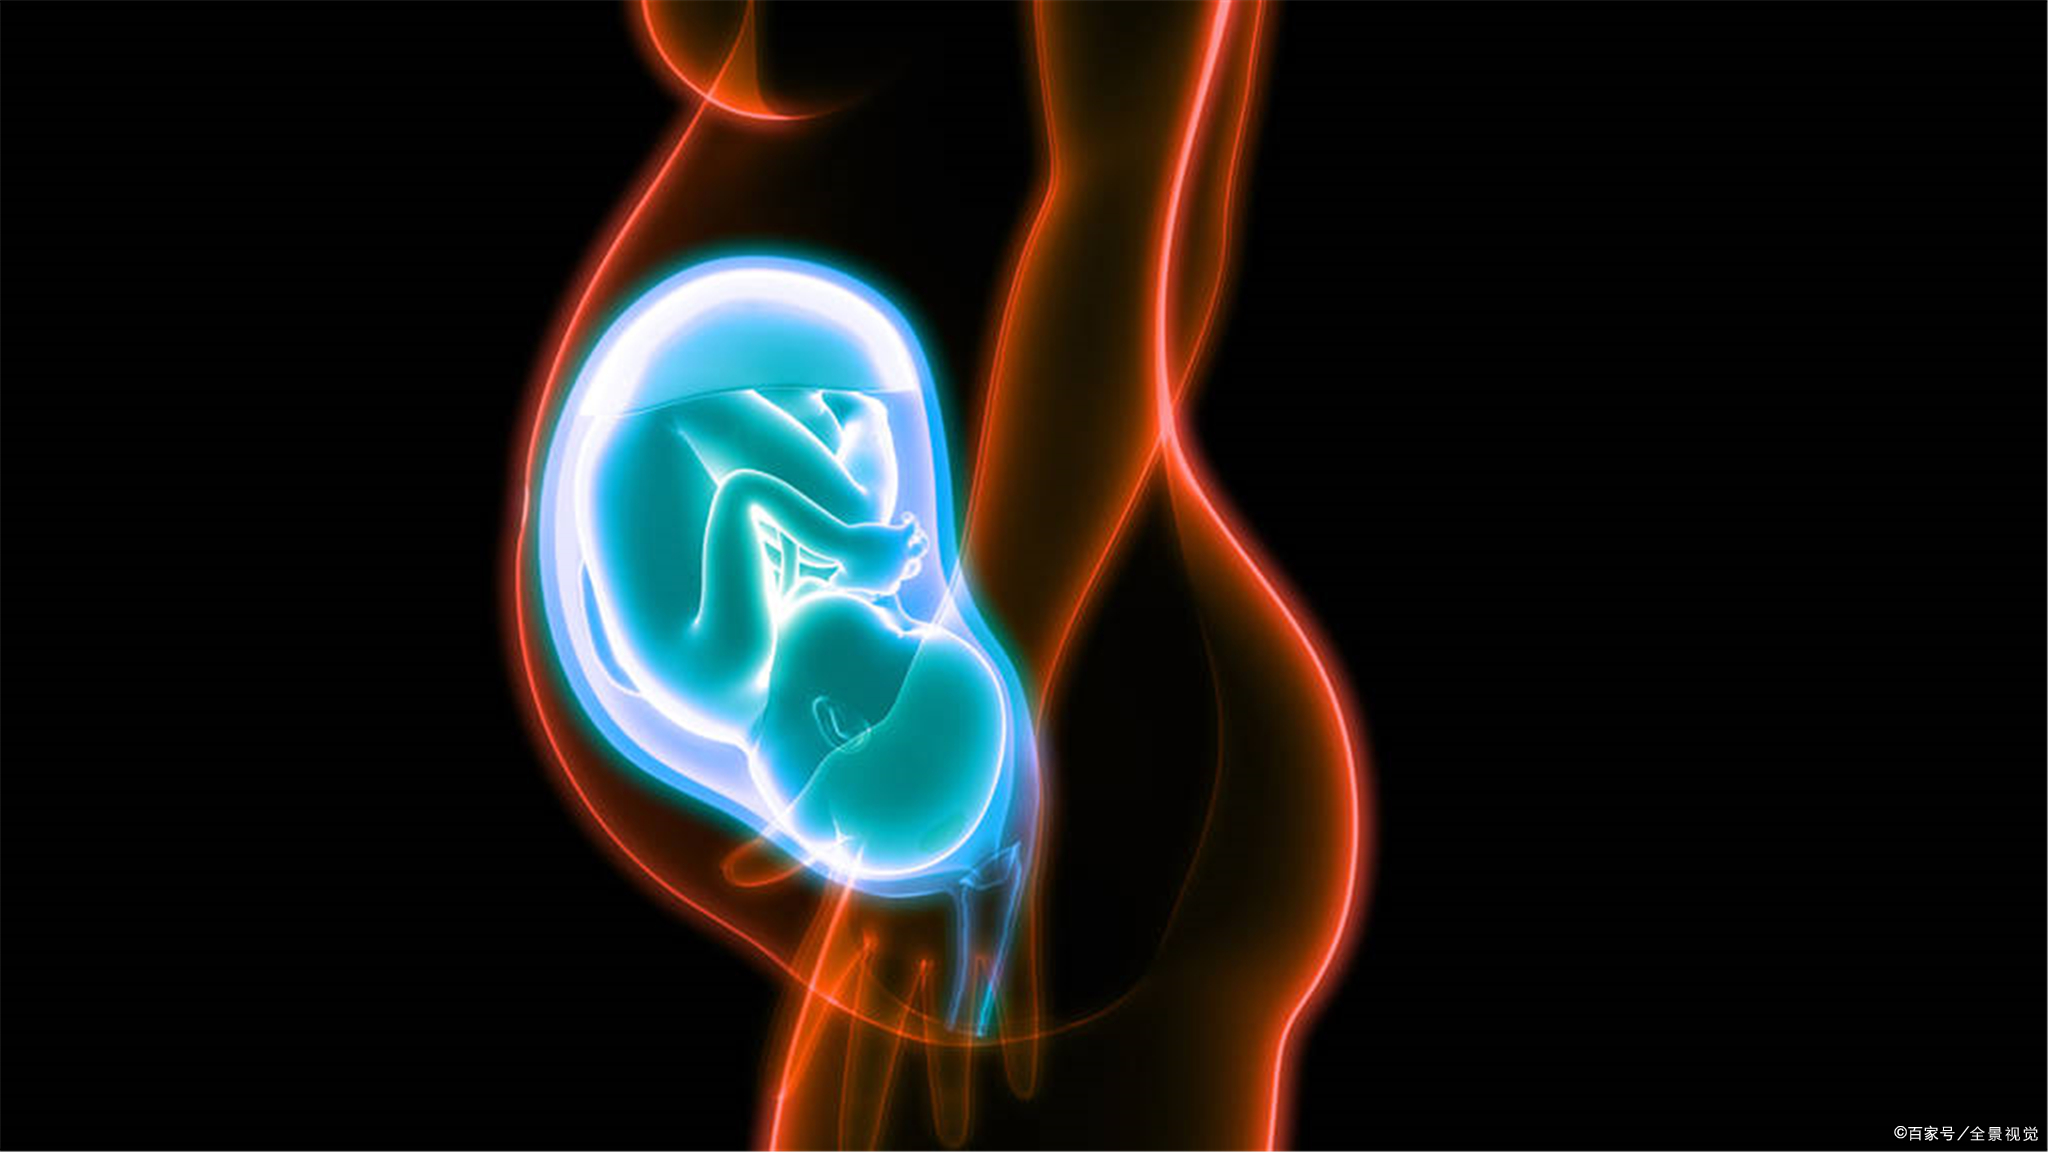

P11 子宫内的胎儿、脐带和胎盘关系的示意图知识补充

1.胎儿生活在母体内,胎儿生长发育过程中所需要的各种营养物质,都是通过胎盘从母体中获得的。如果孕妇喝酒、吸烟(包括被动吸烟)或者吃了某些药品,酒精、*草烟**和这些药品中的有害物质,就会通过胎盘和脐带到达胎儿的体内,对胎儿的生长发育产生不良影响。